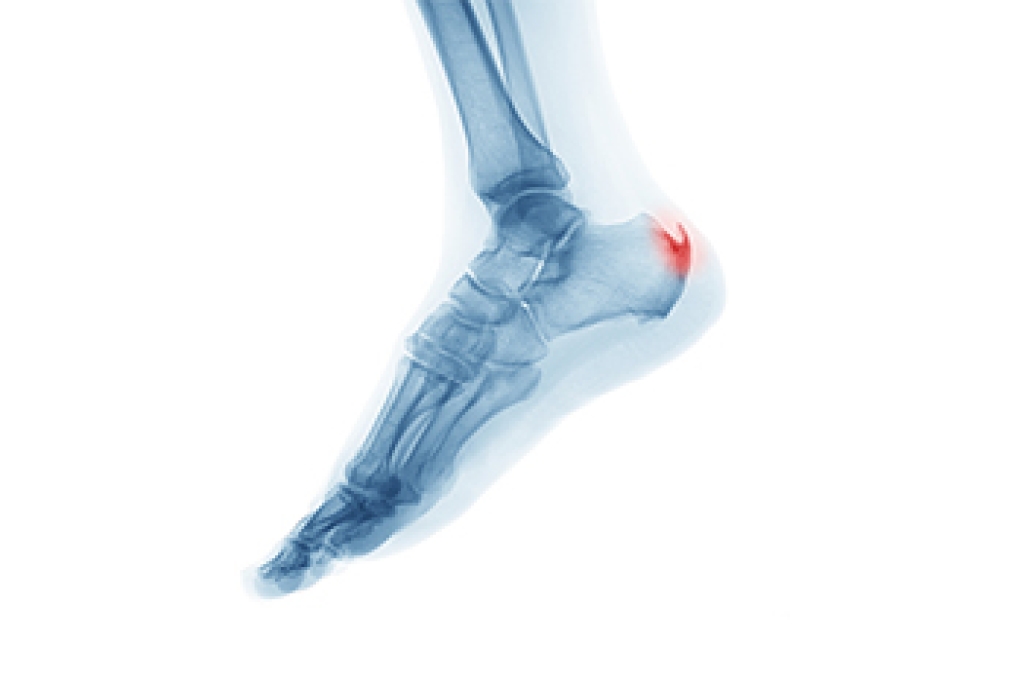

Diagnosis

Due to the wide variety of potential causes of ankle pain, podiatrists will utilize a number of different methods to properly diagnose ankle pain. This can include asking for personal and family medical histories and of any recent injuries. Further diagnosis may include sensation tests, a physical examination, and potentially x-rays or other imaging tests.